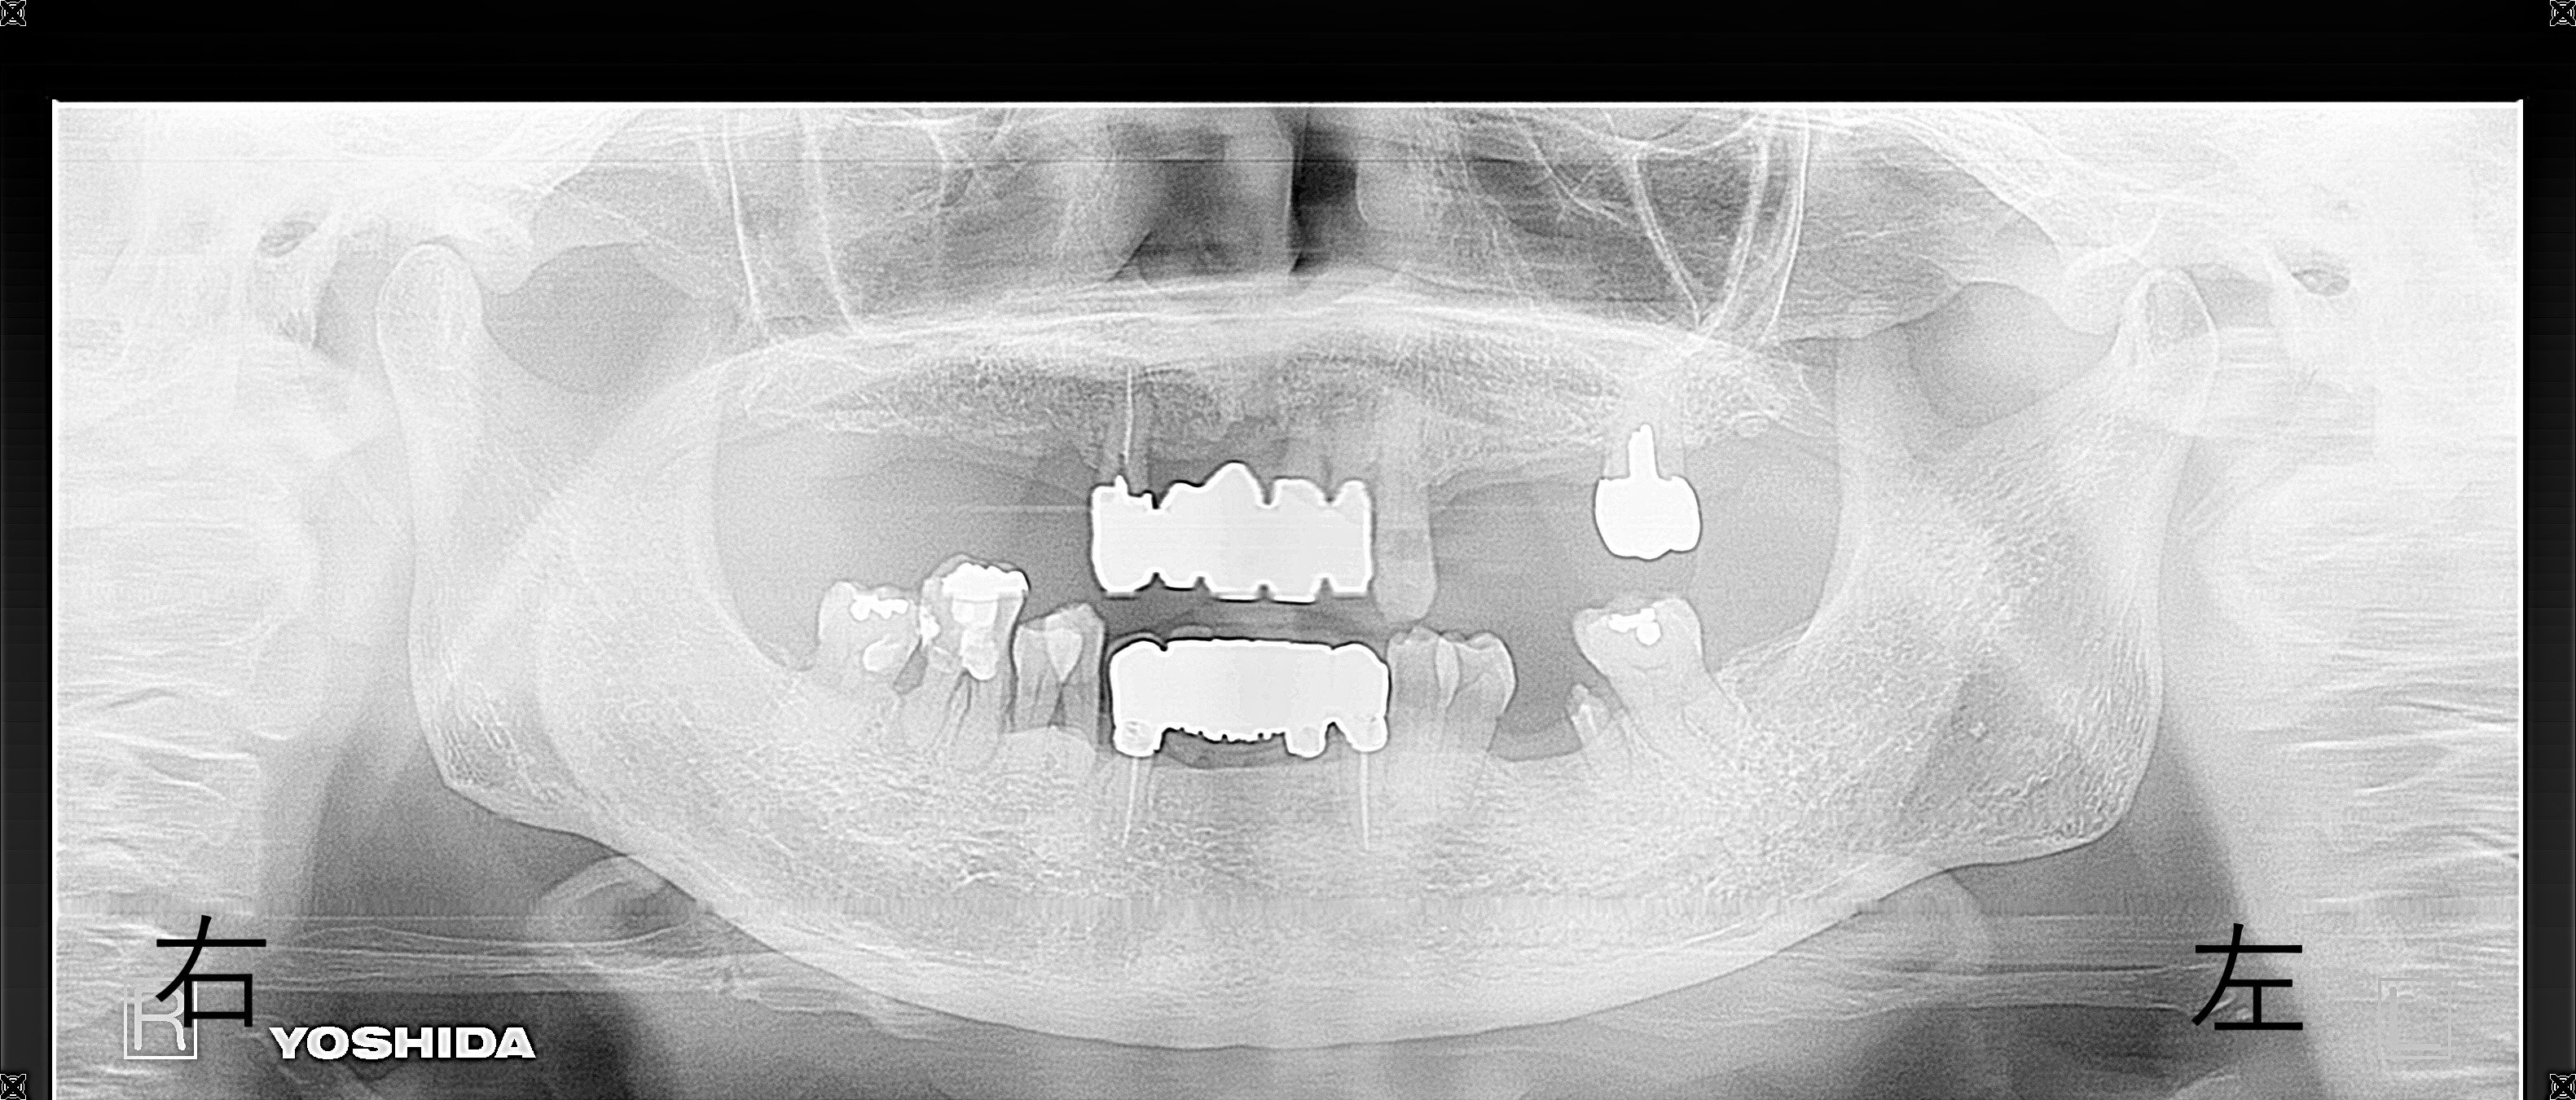

【レントゲンおよび口腔内診査】

歯槽骨の吸収が著しく、全体的な歯周病の進行が確認され、初診時点では詳細な治療計画を立てるのが困難な状況でした。さらに、長期間の義歯不使用により右下奥歯が挺出していた(歯が伸びていた)ことも確認されました。